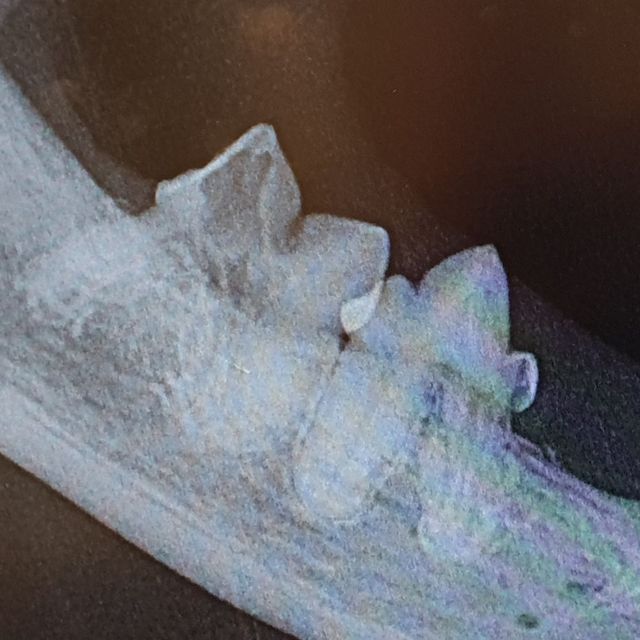

Etter hvert vil slik betennelse utvikle seg fra å være en overflatisk betennelse i tannkjøtt til en dypere betennelse mellom tanna og tannbeinet. Dette er svært smertefullt for dyret, og tanna vil løsne. I de fleste tilfeller vil den eneste løsningen for en slik tann være å trekke tanna. Dette vurderer dyrlegen din ved å gjøre en grundig undersøkelse av tanna og tannkjøttet, og ved å ta røntgenbilder av tanna. Dette må gjøres når dyret er i narkose.

Ved et tannrens hos oss blir først munnen skyllet med et antiseptisk middel. Deretter blir belegg og tannstein fjernet med ultralyd, før en fjerner tannstein under tannkjøttranden med en spesialskrape. Det er svært viktig at all tannstein - også den mellom og på baksiden av tennene fjernes. Deretter blir tanna polert glatt. Dette er viktig ettersom skraping av tannstein vil føre til riper i emaljen som bakterier og belegg vil få godt feste i om det ikke poleres bort. Så blir hver eneste tann undersøkt med en probe for å sjekke at det ikke er lommer i tannkjøttet eller problemer med røttene. Hos oss er også røntgenbilder av alle tennene inkludert i prisen for tannstell.

En tann som er brukket inn til pulpa, der nerven og blodkarene til tanna ligger, er svært smertefullt for hunden. Den blottede pulpaen vil også være inngangsport for bakterier, og vil ofte føre til tannrotsbyller. En slik skade kan i noen tilfeller repareres med rotfylling, dette må vurderes etter undersøkelse og røntgen av tanna. Dersom dette ikke er aktuelt må tanna trekkes.

Ofte er røntgenbilder den eneste måten å sikkert vurdere om en tann må gjøres noe med eller ikke. Hos oss er røntgenbilder av alle tennene inkludert i prisen ved tannrens.

Det er også viktig med røntgenbilder av aktuelle tenner både før og etter trekking, for å sjekke hvordan røttene ligger og ser ut - og for å kontrollere at en har fått med seg alt. Nødvendige røntgenbilder tatt i forbindelse med tanntekking blir det fakturert for.